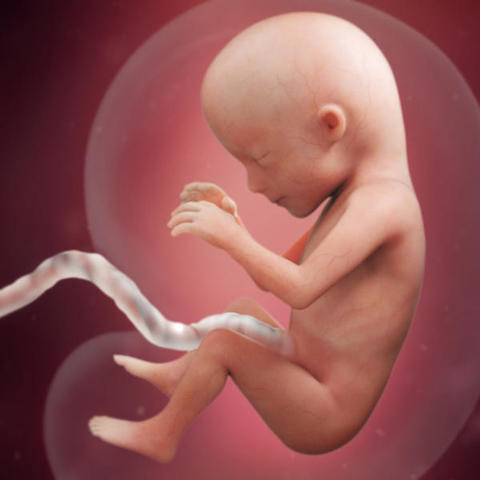

• Semana 14

Semana 14

Las orejas del feto se encuentran implantadas a ambos lados de la cabeza y también los ojos se han acercado; tanto que ya se distingue el puente de la nariz.

- Su cabeza sigue siendo mucho más grande en proporción con su cuerpo.

- Su hígado es aún muy grande, porque tiene que fabricar células sanguíneas

- Su piel sigue siendo tan sumamente fina que a través de ella se pueden ver algunos de los órganos internos y los vasos sanguíneos.